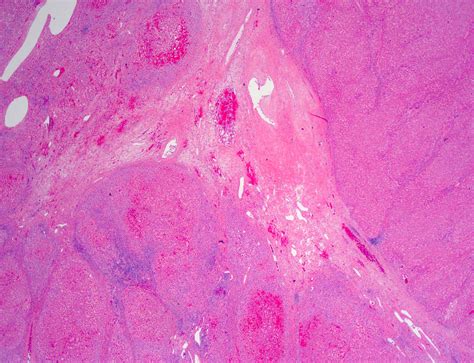

• Liver Biopsy: In some cases, a liver biopsy may be performed to confirm the diagnosis. This involves taking a small sample of liver tissue for examination under a microscope.

• focal nodular hyperplasia liver pathology